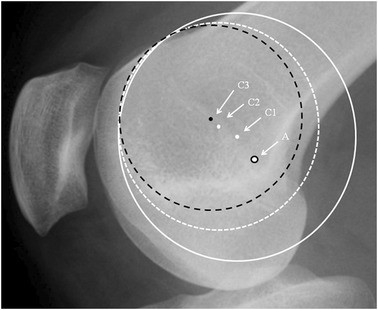

Lateral radiograph of the knee showing different circles depending on how the observer chooses the best circle-fit to the dysplastic trochlea curve: Schöttle’s point: black rimmed spot (A). Centres of white circles: white spot (C1) solid circle and (C2) dashed circle. Centre of black circle: black spot (C3)

It was noticeable that when applying a circle to the groove line in the PFI cohort, the circle could be placed to touch two points on the groove, e.g., B and D (Fig. 3) or the circle could match much of the groove (Fig. 4). In the control cohort the groove matched a circle. In Fig. 3, for a patient with TD, it can be seen that the isometric point is anterior to Schöttle’s point, and the radius of the circle from Schöttle’s point to the apex of the boss is longer than that for the best-fit circle. This would result in a significantly anisometric graft if the Schöttle’s point was used as the femoral tunnel position. In Fig. 4, in TD, isometric point moves anteriorly as the circle is made smaller. This implies that there is potential for significant error in the isometric point position in TD. A much more complex methodology is needed requiring 3D reconstruction and analysis of the tracking of the patella to define the femoral tunnel position in the presence of TD. This is not appropriate for the surgeon in a clinic. Interestingly, using 3D CT scans in different degrees of knee flexion, Blatter et al. [4] only found one isometric point in 10 normal knees when measuring the MPFL length with a maximal length difference during knee flexion of 10 mm. They also noted that for most, the optimal tunnel position was slightly anterior to Schöttle’s point. It would be interesting to know how this correlated with the lateral plain radiograph.